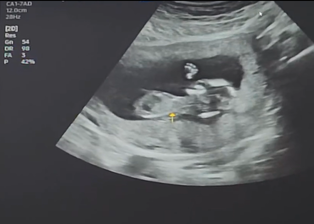

이진아, 결혼 6년 만에 임신 소식 전해! 🎉

최근 가수 이진아가 결혼 6년 만에 임신 소식을 전했습니다. 이진아는 자신의 소셜 미디어를 통해 팬들과 소통하며 기쁜 소식을 전했는데요, 많은 이들이 그녀의 행복한 소식에 함께 기뻐하고 있습니다. 이번 포스팅에서는 이진아의 결혼과 임신 소식, 그리고 그녀의 음악 활동에 대해 자세히 알아보겠습니다.

이진아는 6일 자신의 인스타그램에 임신 소식을 전하며 "잘 지내고 계시지요? 새로운 소식이 있어서 글을 올려보아요"라는 메시지를 남겼습니다. 이 글은 많은 팬들에게 큰 감동을 주었고, 그녀의 행복한 소식을 함께 나누고 싶어하는 팬들의 댓글이 이어졌습니다.